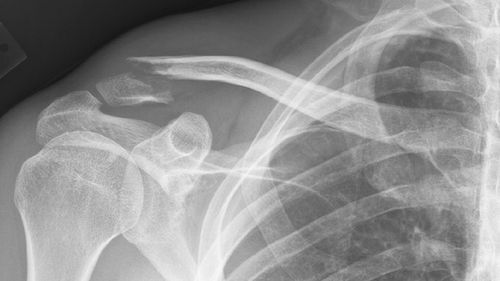

FlexBone – materiał do łatania dziur w kościach 1Złamana kość; fot. starpause kid, Flickr.